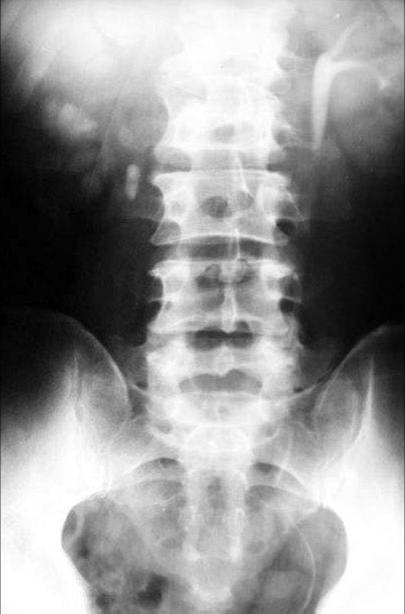

照片名称:肾性骨营养不良,cppd